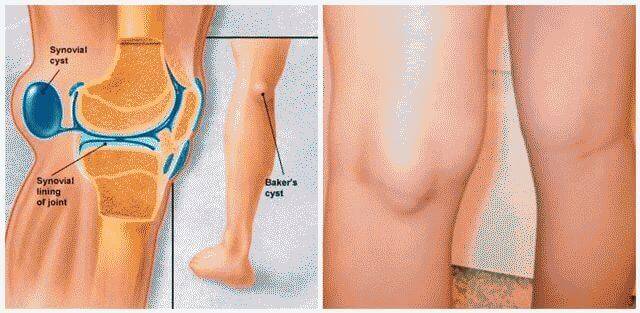

Заболевания и медицинские снимки: Жидкость в коленной чашечке